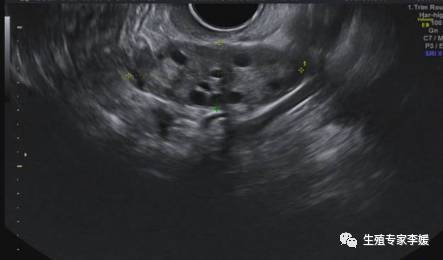

开始进入试管婴儿的周期后,医生需要结合激素的值和卵泡的发育情况来决定开始促排卵的时机、促排卵药物的剂量和应用时间,后面需要根据激素的值和卵泡的生长情况来调整用药,直到卵泡长到合适的大小,使用hCG促卵泡最终成熟,最后在超声引导下取卵。在超声监测卵泡的同时,医生也会关注内膜的情况,来决定是否适合新鲜周期移植。在取卵后,也需要复查激素和超声,来看是否有卵巢过度刺激的风险,盆腹腔是否有积液,是否适合做新鲜周期的移植。所以,在促排卵期间需要频繁的做超声检查,在卵泡快成熟的时候甚至可能每天都需要做超声监测卵泡情况。